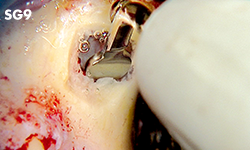

Unilateral anterior mandibular sampling

Excision of bone torus

Anterior mandibylar harvesting

Mandibular harvesting at approach stage

The cutting part is bone torus